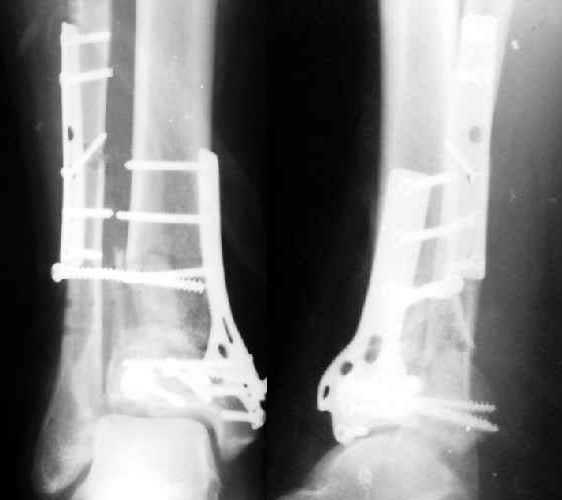

Полтора месяца назад мужчине 45 лет выполнена открытая репозиция дистального отдела большеберцовой кости и внутренняя фиксация (снимок 1).

На другой ноге - переломы нескольких плюсневых костей. Из-за сопутствующих урологических проблем через две недели перевели в другое учреждение, там был вынужден ходить с костылями с нагрузкой на обе ноги.При контрольной явке к нам через месяц обнаружилась несостоятельность фиксации (снимок 2). Какие выходы их положения можно тут предложить?